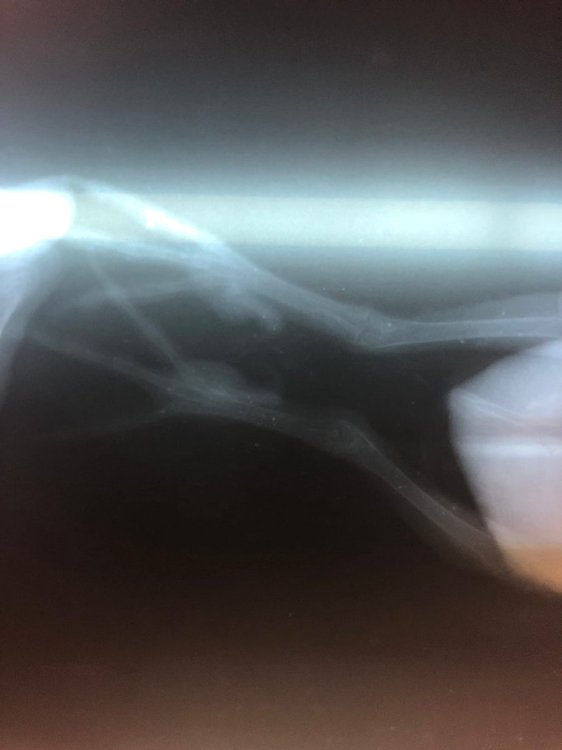

Juan_Esteban_Vazquez Опубликовано 23 февраля, 2022 Автор #87 Опубликовано 23 февраля, 2022 @Zosia, здравствуйте. Сегодня сделали рентген. Скрытый текст

Zosia Опубликовано 22 февраля, 2022 #84 Опубликовано 22 февраля, 2022 1.Сорьент, смекта или иное,натощак, до 2 мл (споить-скормить за час). 2.Ампульный ГК, 0,2 мл 2 р/сутки, 7 дней. 3.РЕНТГЕН. 4.Цеф уже ни к чему. Оставляете только НПВС (ибупрофен+тревматин, нимулид+травматин) 5.Мидокалм (толперизон)- доза 0,6 мг на 100 гр веса в сутки, вместе с НПВС. Все прочее- после рентгена. Очень желательно микроскопия помета , в окраске люголем. Искать кристаллы. 1